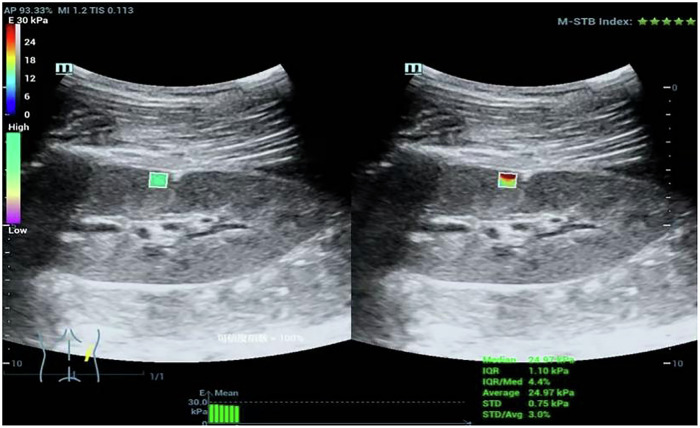

The elasticity of renal tissue was measured by SWE in STQ mode, and the results were expressed by Young’s modulus (YM). The Mindray Resona 7-T ultrasonic device was used, equipped with an SC5-1U convex array probe. All images were obtained from the patients in the lateral decubitus position while holding their breath by two skilled radiologists (Y.F.F. and L.H.X., with 18 years of experience in US imaging). The sample box was placed in the right renal cortices of the middle portions (Fig. 1). A region-of-interest (ROI) of fixed size was chosen for each measurement. The motion stability (M-STB) index located in the upper right corner of the screen should be no less than four stars. The final elasticity values represent the mean of six measurements, with the interquartile range (IQR) to median ratio (IQR/M) between measurements less than 30% (calculated automatically by Mindray Resona).

Fig. 1.

Ultrasound elastography in the PNS patients